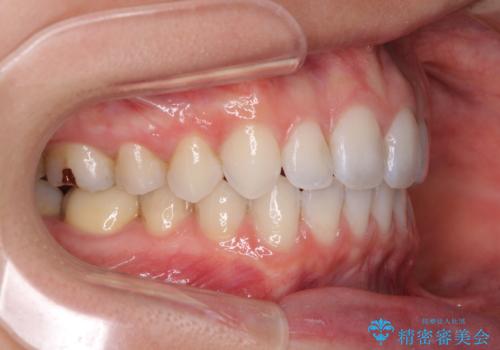

- 奥歯の虫歯と前歯のデコボコや突出感を気にして来院された患者様です。

上顎歯列が、下顎に対して前方にありましたが、口元に出っ歯の印象がなかったため、親知らずを抜歯した上で、上顎歯列全体を後方に移動させることとしました。

矯正治療後は、奥歯の虫歯や銀歯を補綴・修復治療することとしました。

上顎歯列を下顎に対して4mmほど移動させる必要があったため、治療は長期化することが予想されましたが、患者様にはこちらの期待以上にゴムかけなどに協力いただき、補綴治療も含めて2年強で終えることができました。